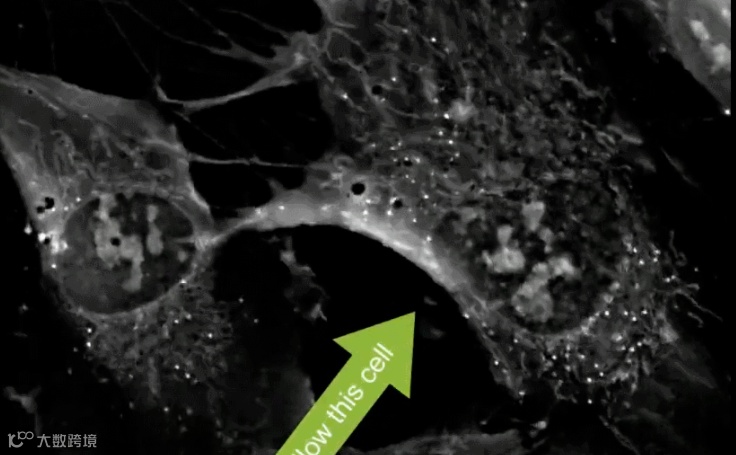

△ 逐渐收缩成球体的间充质干细胞

紧接着,细胞开始进入最旺盛的繁殖阶段,细胞分裂增多,开启成指数级增长模式。

增殖到一定程度,细胞数量几近饱和密度,染色体复制完成后再来一个分身式分裂,从而一分为二,实现了细胞的大动作增殖。

△ 细胞一分为二,开始复制性增殖